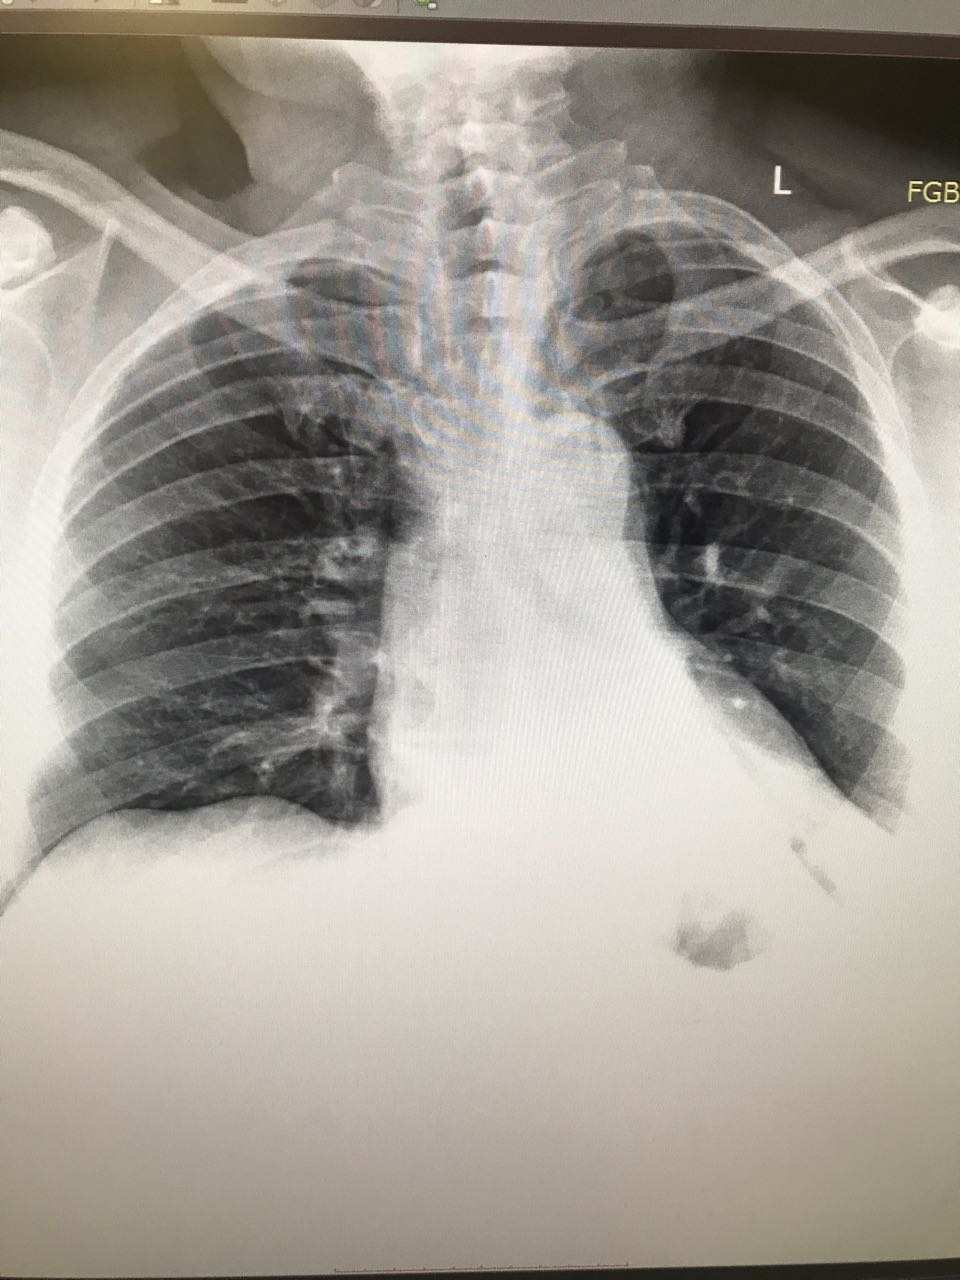

Рак преимущественно левого легкого

Обсуждалось в Госпитале Ослабленных Сердец